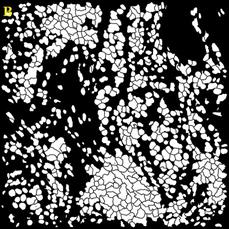

В ходе работы выполнен анализ трех изображений, с площадью покрытия клетками окна среза 80%; и 40%, а также наличия размытых границ клеток (Рисунок 3).

Рисунок

3 – Примеры обрабатываемых изображений. А – площадь покрытия клетками окна среза 80%; Б – площадь покрытия клетками окна среза 40%; В – наличия размытых границ клеток. Далее – изображения 1, 2, 3, соответственно

Для сравнения качества сегментации использовались маски ядер и клеток. Маски, полученные при помощи разработанного алгоритма, показаны на Рисунок 4.

4 – Результаты обработки изображений А – маска ядер изображения 1; Б – маска клеток изображения 1; В – маска клеток изображения 2; Г – маска клеток изображения 2; Д – маска ядер изображения 3; Е – маска клеток изображения 3

Разработанные алгоритмы показали хорошее качество сегментации для изображений с большим и малым количеством клеток. Однако алгоритм сегментации требует доработки при работе с нечёткими изображениями. В этом случае маска клеток содержит искаженные границы клеток для большинства ядер.

Количество клеток на первом изображении составляет 848, на втором 229, на третьем 218. Количество пропущенных либо раздробленных ядер и клеток не превышает 5% от общего числа клеток.